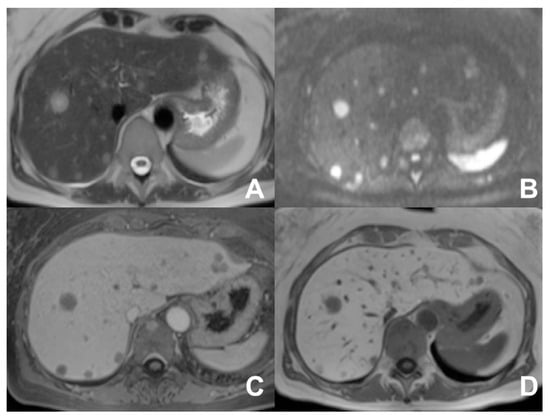

| DWI b 0–50–400–800 | AXIAL | -- | -- | Restricted diffusion most likely malignant | |

| DWI b 0–50–400–800 | AXIAL | -- | -- | High signal in b 800 suspicious for HCC | |

| DWI b 0–50–400–800 | AXIAL | -- | -- | DWI b50 increases the sensitivity of mets detection | |

| GRE T1 3D DYNAMIC | AXIAL | PRE-ART 25″-PORTAL 70″-LATE 180″ | YES | HBP increases the sensitivity of metastases detection | |